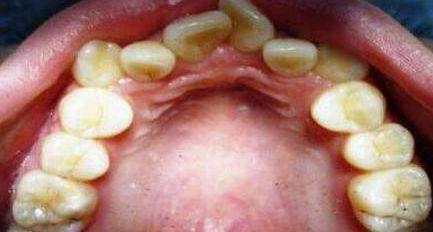

口腔中有没治疗的龋齿、残根、残冠、不良修复体、牙龈炎、牙周炎及口腔粘膜病等都可以引起口臭。

其中,深龋窝洞内经常容易残存食物残渣和菌斑,细菌经过发酵分解,产生臭味;